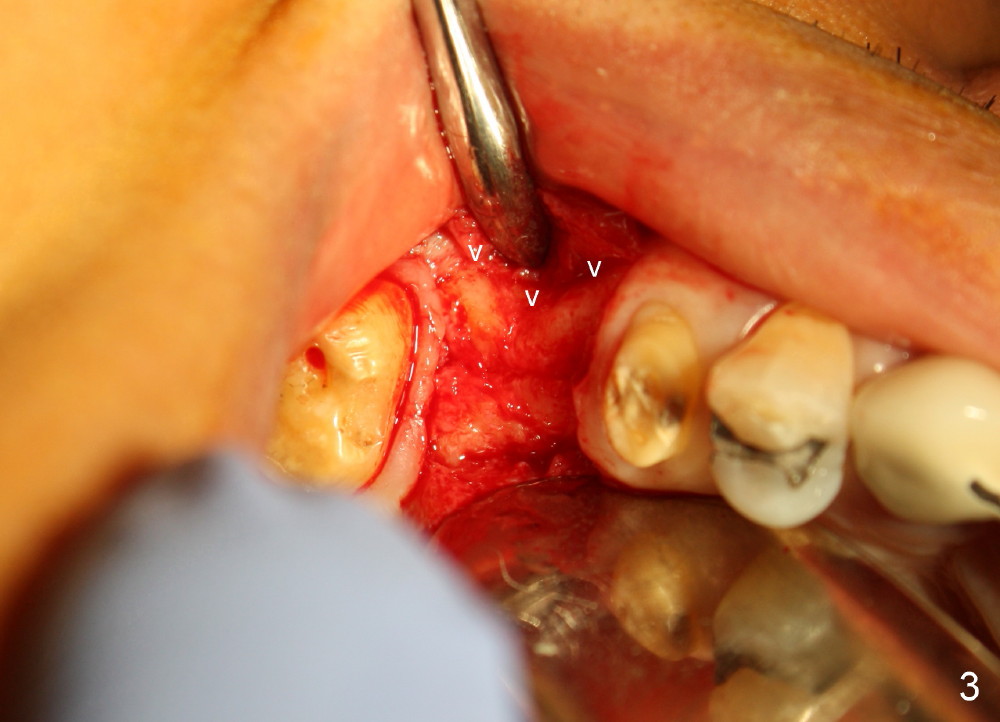

The bone density (Fig.1 white *) at the edentulous area (#3) is lower than that at the dentulous one (black *, 50 year-old man). The buccal plate is also atrophic and concave (Fig.2,3 arrowheads). A series of bone expanders are used to form osteotomy (following 1.6 mm pilot drill) at the depth of 14 mm (Fig.3 E 3.0 mm in diameter). When the last expander (4.3 mm) is removed from the osteotomy, the buccal plate appears to have been moved buccally (Fig.5 arrowheads). A 5.3x14 mm submerged implant (Fig.6 I) is placed with insertion torque >35 Ncm. The buccal plate seems to improve following placement of an 8.2 mm healing abutment and suturing (Fig.7). No bone graft is used. The buccal plate remains normal 12 days postop (Fig.8). It is slightly concave 3 months postop (Fig.9) with minimal bone resorption at the crest (Fig.10 (H: healing abutment),11 (A: cemented abutment). Nine months post cementation (12 months postop), bone resorption at the crest remains minimal (Fig.12) while the buccal plate (Fig.13 *) at #3 remains strong. Bone loss appears not to get worse 22 months post cementation (Fig.14). Soft and hard tissues remain healthy around the implant crown 3 years (Fig.15) and 3.5 years (Fig.16,17) post cementation.